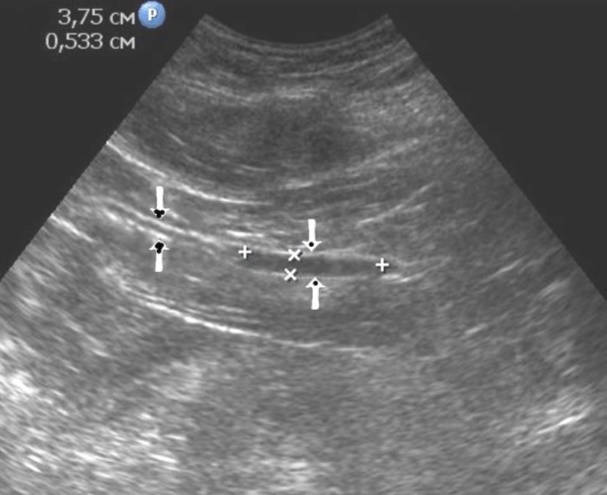

Distal gastric cancer was observed in 24 (39,3%) cases and contributed to the development of pyloric stenosis: in 6 (9,8%) cases it was compensated, in 18 (29,5%) – was sub compensated. The layers of the wall were not differentiated in all patients with sub compensated pyloric stenosis. In the case of compensated pyloric stenosis, the thickness of the affected area was 10,2±2,9mm, the length was 27,1±6,2mm, the diameter of the pylorus was 8,3±0,8mm (Figure 14). Among patients with sub compensated pyloric stenosis, the thickness of the stomach wall was 19,8±4,1mm, the length was 43,6±4,5mm, the pyloric diameter was 4,3±1,1mm (Figure 15).

Figure 15.Distal gastric carcinomas of diffuse infiltrative form of T3 stage. Sub compensated pyloric stenos (arrows). The thickness of the anterior wall of the stomach is 9,13 mm, extent of the affected area – 7,84 cm. On an empty stomach in the cavity of the stomach is determined an a large amount of fluid. The diameter of the pyloric canal is about 6 mm.